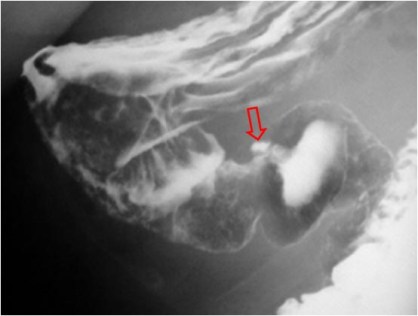

Signo visible en el tránsito baritado superior (EGD) que permite diferenciar una úlcera de una imagen de adición no ulcerosa (divertículo, pseudodivertículo, deformidad quirúrgica,…). Cuando la colección de bario es elíptica, la orientación del eje largo es un indicador del origen de la lesión. Si es paralelo a la luz indica úlcera; si es perpendicular, representa una lesión no ulcerosa.

En la imagen, una úlcera pilórica (flecha) visible como una imagen de adición de bario de forma elíptica irregular, cuyo eje mayor es paralelo a la luz antral.

En esta fotografía vemos otra imagen de adición de bario elíptica pero esta vez junto al fundus gástrico. A diferencia de la anterior, el eje mayor de esta elipse es perpendicular a la luz gástrica, por lo que no corresponde a una lesión ulcerosa. Se trata de un divertículo fúndico.